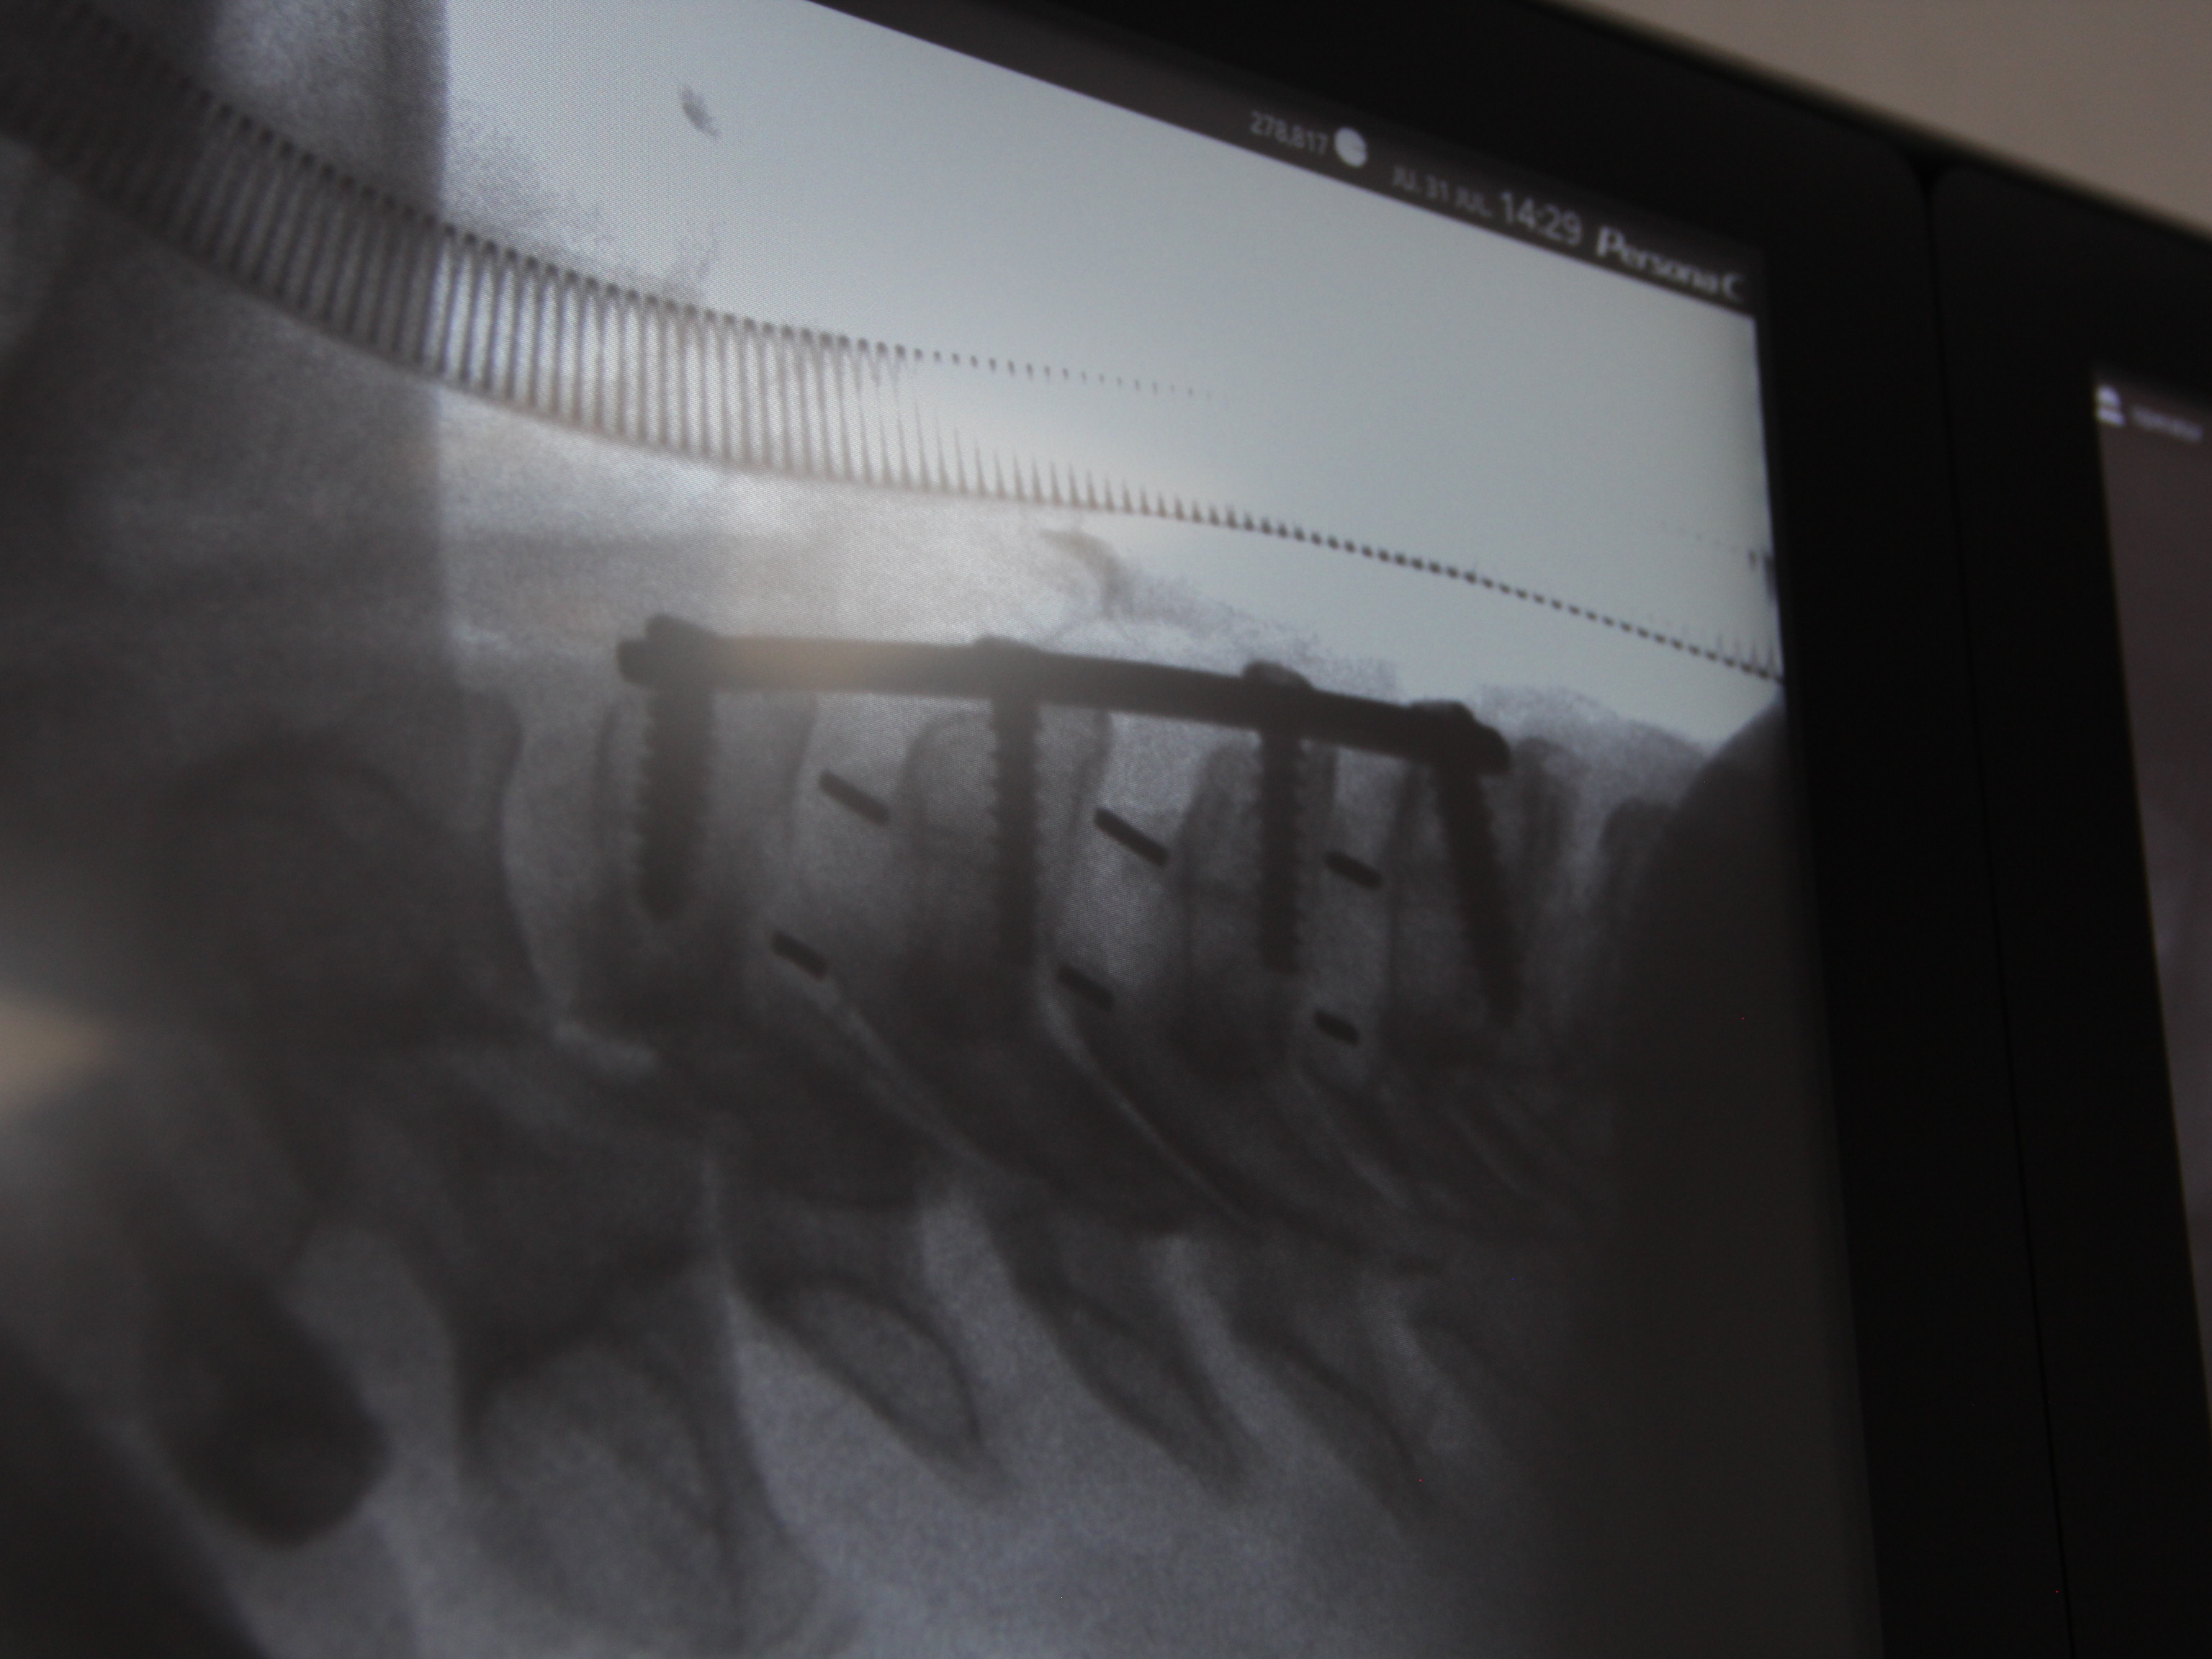

SURGERIES